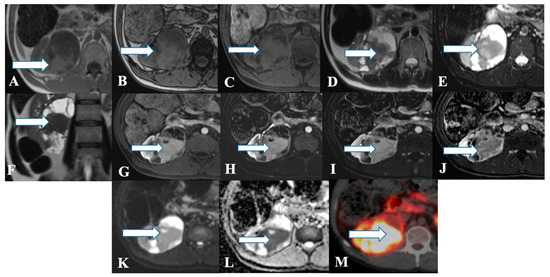

Figure 4. A 45-year-old female with renal NENs. MRI axial T1 (A) in phase, (B) out of phase, (C) 3D axial, (D) T2, (E) T2 fat saturation, (F) coronal T2, (G) post-contrast dynamic, (H,I) dynamic subtraction images, (J) delayed postcontrast axial, (K) DWI, and (L) ADC show a large right renal mid and lower pole mass (arrows) measuring 6.6 × 7.1 cm showing central enhancing solid component with restricted diffusion and peripheral cystic component. Pathology revealed a neuroendocrine tumor. (M) Axial fused PET/CT images using Gallium 68 Dotatate show heterogeneously avid DOTATATE uptake of the mass (arrow), in keeping with biopsy-confirmed right kidney neuroendocrine carcinoma.